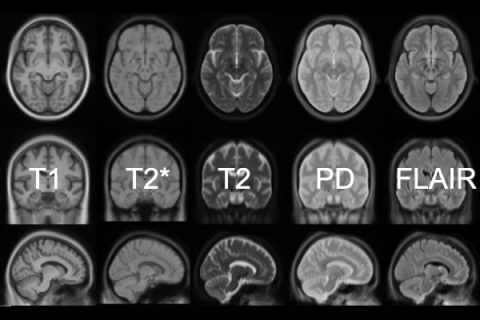

Anatomical (structural) MRI Techniques

CORE GIfMI actively maintains a full library of optimized sequences, including:

- T1-weighted imaging

- T2-weighted imaging

- T2*-weighted imaging

- Fluid Attenuated Inversion Recovery (FLAIR)

- Proton density-weighted imaging

- 3D imaging: VIBE, SPACE, MP-RAGE, GRASP-VIBE, etc.

- and more